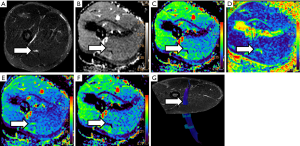

Several parameters are derived from DWN and DTN studies, which allow quantifying diverse pathophysiological conditions in PN (Figure 3).

ADC results from the difference in signal intensity terms between both the low and the high b values. ADC reflects the water displacement in the extracellular space without consideration of water molecules motion direction (19). High ADC values are consistent with increase of this extracellular space, usually representing edema regardless of its origin (i.e., trauma, compression or fiber disruption). ADC is expressed in mm2/s, and allows quantifying and monitoring the edema within PN or plexus. In PN pathology, it is less common to find low ADC values, which usually indicates the presence of a solid lesion with reduced extracellular space such as neurogenic tumors (20).

FA is an index of fiber organization, which reflects the integrity of axonal bundles and the directionality of water movement delimited by physiological barriers such as myelin sheaths, endoneurium, perineurium or epineurium. FA is a dimensionless parameter, which values vary from 0 to 1. An FA value of 0 is considered the lowest level of fiber organization, the highest isotropic diffusion. A FA value of 1 is related with the maximum anisotropy or the highest level of fiber organization (21). PN usually don’t show the highest FA values because, as previously explained, there are other directions of water movement within the nerve fibers. However, healthy PN usually point FA values of about 0.6 with physiological variations depending on the evaluated (proximal or distal) area, the patient age and other factors. Previous reports have demonstrated that there is a variation in FA values that correlates with the age of the studied subjects (22). These variations have to be taken into account when DTI studies are used for PN evaluation in order to avoid false positive or negative results. FA has a very high sensitivity for lesion detection, even in apparent normal PN on conventional morphological studies (2).

MD is a parameter derived from DTI that is the result of the average of the three main eigenvalues (23). As MD considers the main three directions of the space, allows assessing more accurately the water displacement at extracellular space in comparison to ADC, which does not consider any water direction. It is measured in the same units than ADC (mm2/s), with parallel behaviour of both parameters in different clinical scenarios.

AD (mm2/s) corresponds to the measure of the main eigenvector. It reflects the water diffusion along the main nerve direction and can be consider a surrogate biomarker of axoplasmic flow integrity. In the main direction of PN, water can move freely as no barriers exists that impede its motion, thus AD values are usually higher than ADC or MD ones (24). AD values may vary according to the type of PN injury and its location; in fact, theoretically, low AD values reflects a proximal interruption of axonal flow. However, it is not uncommon to find an increase of AD values secondary to the overall increase of water diffusion in neural damage (25,26).

RD (mm2/s) is the average of the two perpendicular (minor) eigenvalues. It reflects the degree of restriction or freedom of water diffusion within the short nerve axis. Due to the presence of myelin sheaths, the movement of water molecules in the perpendicular (short) axis is very limited (24). Thus, normal PN will show low RD values as they have it physiological barriers intact. In the other side, PN with traumatic or other kind of myelin damage will show higher RD values than normal PN as water molecules find no obstacles for free diffusion. In these terms, several studies have proposed to consider RD as a potential biomarker of myelin integrity not only for lesion detection but also for treatment monitoring. Normalization (decrease) of RD values in a damaged nerve may reflect a re-myelination process (27).